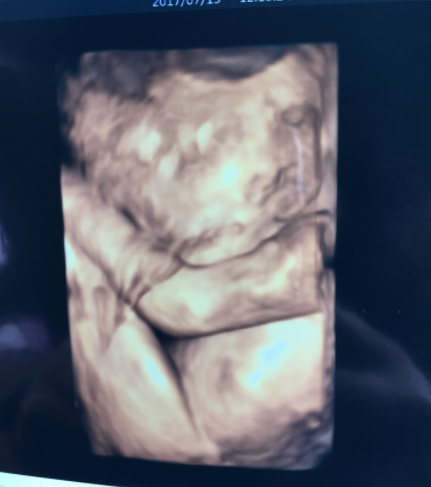

26週2日(26w2d・女の子)|chigusa903 さん(34歳)

エコー写真撮影時のエピソード:

妊娠中は坐骨神経痛、ひどいつわり、耳の不調なと毎日毎日違う症状に悩まされました。産院から4Dエコーが撮れるということで、撮ってみたら、はっきり顔が見えて、あっかんべーをしていて家族みんなで笑った記憶があります。辛い症状の毎日でもリアルな表情を見て赤ちゃんが産まれた時の日々の実感が湧いてきました。実際産まれて、写真そっくりで、舌は良く出す子です。